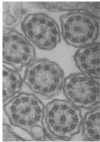

What does the following image indicate?

Cliated epithelia, some of the cilia have a lack of central dynein rings suggestive of primary ciliary dyskinesia